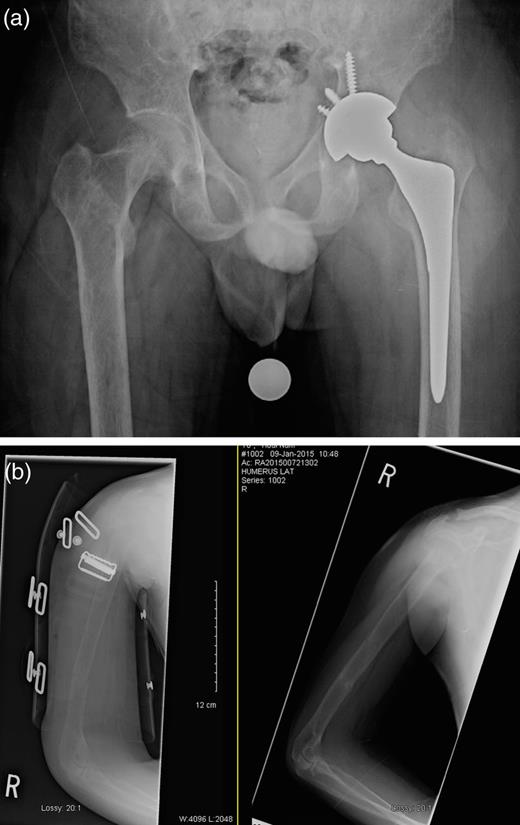

(a) Left femoral neck displaced subcapital fracture and (b) right humeral shaft segmental fracture.

One day after sustaining this injury, the patient underwent an uncemented left total hip arthroplasty (THA) (Fig. 2), and acetabular fixation was supplemented with multiple screws, and he maintained touch-down weight bearing for 6 weeks postoperatively. His right humeral fracture was managed conservatively using a functional brace. A parathyroidectomy was performed 2 days later. The histopathology report confirmed the diagnosis of a parathyroid adenoma. Within 3 days postoperatively, the PTH level had decreased to 4.9 pmol/l, and the calcium level had returned to normal at 2.42 mmol/l. The calcium level continued to fall, and 2 weeks after the parathyroidectomy, it had reached 1.70 mmol/l. After a further 20 days, it started to normalize and then continued to remain stable, as shown in Fig. 3.